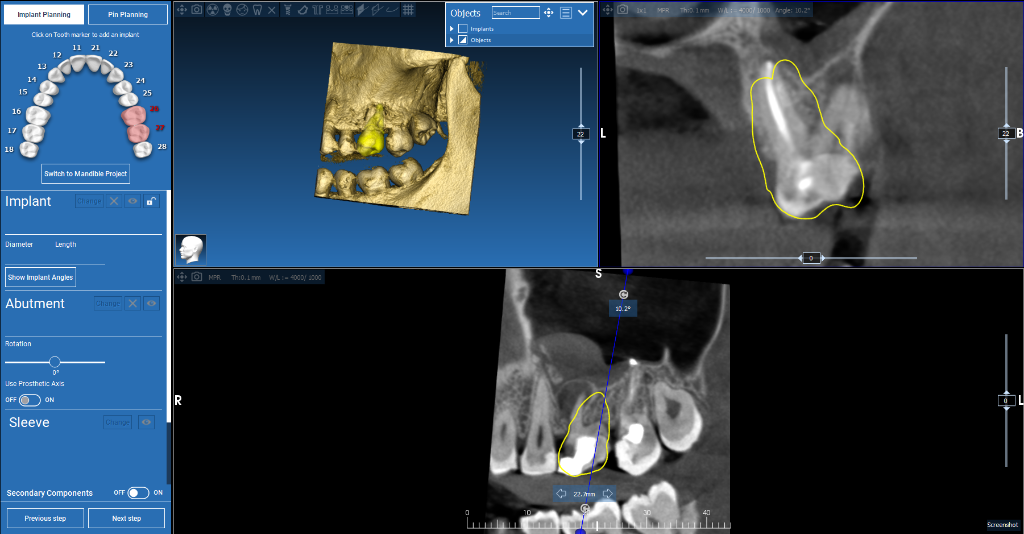

Surgical Guide Design Portfolio

Dental implant guides, apical resection & autotransplant cases from our practice

Maxillary Implant Case — 3 Implants

Tooth-supported guide for 3 implants in the upper jaw. Digital planning with precise implant positioning.